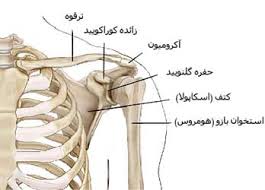

قیمت: 32٬000 تومان - دسته بندی فایل: پاورپوینتپاورپوینت استخوان ترقوه

فروش ویژه پاوزپوینت حرفه ای استخوان ترقوه با تخفیف استثنایی قیمت 63 هزار تومان تعداد اسلاید: 15 اسلاید